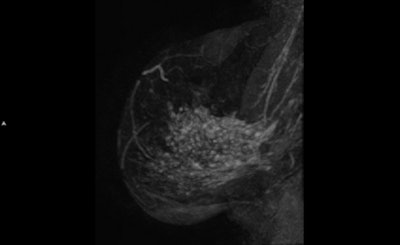

A 45-year-old woman with invasive lobular carcinoma (ILC) in her right breast shown as heterogeneous segmental nonmass enhancement of 75 mm on preoperative breast MRI (axial and sagittal maximum intensity projection). The ILC was mammographic occult and only 8 mm on ultrasound. After pathological proof of the more extensive size, the treatment was altered to mastectomy. All images courtesy of Kenneth Pengel and Dr. Claudette Loo.